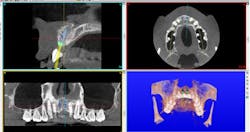

The authors noted a paradigm shift in their practices over the last several years. Hattingh et al. published a technique article regarding immediate placement of ultrawide diameter implants in molar sockets.14 Instead of the more traditional protocol that involved diagnosis of a nonrestorable molar with subsequent extraction, graft, osseous healing, implant placement, osseointegration, and implant restoration, the authors adopted an accelerated treatment protocol due to the availability of site-specific implants.

Site-specific implants for specific and varied implant surgical and prosthetic therapies allow clinicians’ choices regarding precisely designed products for individual clinical applications. These implants have been developed to provide improved primary stability, avoid/minimize preimplant bone grafting procedures, and allow for improved soft- and hard-tissue preservation around implants.4,5 Site-specific implants can also accelerate treatment by placing specific implants directly into extraction sockets immediately after tooth removal. Furthermore, if primary stability is optimized, site-specific implants can be loaded sooner, which usually leads to fewer patient visits, better soft-tissue profiles, and quicker overall treatment.5-9

Anatomical constraints at implant sites often present a conflict between surgical and prosthodontic prerequisites for screw-retained implant-supported prostheses. Howes published the use of a dual-axis implant designed to help clinicians overcome these challenges by facilitating accurate surgical placement and prosthetic simplicity, as well as improved biomechanics and enhancedSince the authors have adopted accelerated treatment protocols with site-specific implants, they both have noted increased acceptance rates, as well as growth in implants placed and restored. Table 6 illustrates the increased acceptance rate for implant treatment in both practices. Data reflects patient acceptance of implant treatment at the first consultation/clinic visit.